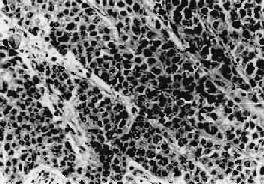

(1)移行细胞癌Ⅰ级:癌组织呈乳头状,乳头表面被覆的移行上皮较厚,细胞层次较多,缺乏从底层到表层由柱状细胞到扁平细胞逐渐分化的现象。细胞核大小不甚一致,有些较大染色较深。核分裂像可见,有的局部区域稍多,且不限于基底层(图12-32)。有些癌细胞可浸润固有膜。

图12-32 膀胱移行细胞癌 Ⅰ级

肿瘤乳头状,被覆上皮细胞层次增多,部分排列不整齐,核大小不甚一致